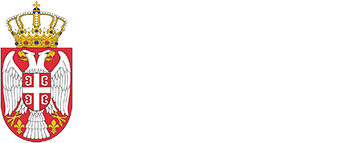

Рендгенски снимак грудног коша

Рендгенски зраци су једна врста зрачења, а људи се са њима углавном сусрећу приликом дијагностификовања поломљене кости или прегледа зуба.

Здравствени радници могу да контролишу ову врсту зрачења помоћу рентген апарата. Када се пацијент постави у рентген апарат, прецизно контролисана доза зрачења пролази кроз циљану област на телу. Дебљи и гушћи делови тела као што су кости пропуштају мање рендгенских зрака, а тањи више. Специјализовани детектор апсорбује шаблон зрака након што они прођу кроз третирани део тела и тако дају снимак унутрашњости тела и промена на њему.

Приликом COVID-19 тестирања, рендгенски снимци грудног коша се користе како би се стекао увид у плућно ткиво пацијента. Ово се пре свега примењује код COVID-19 пацијената са респираторним симптомима, али се рендгенски зраци користе и за праћење напредовања болести и доношење даљих одлука у процесу лечења, као што су одлуке да ли пацијента послати на болничко лечење или, у случају озбиљних симптома, на СТ скенер.

„Пошто су рентген апарати углавном расположиви у домовима здравља, многи здравствени радници већ имају приступ овим машинама у борби са COVID-19 висрусом,“ рекао је Пелит. „Неки од ових апарата су мобилни, лагани, лаки за руковање и лако се врши њихова деконтаминација, што је од пресудног значаја за време пандемије, нарочито у тријажним деловима или привременим болницама.“